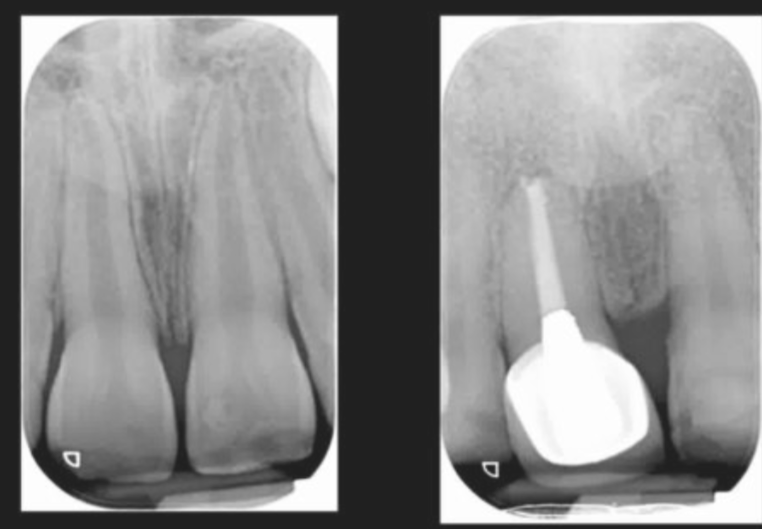

what would you expect to see on a radiograph of normal periapical tissues?

A

• radiolucent (black) line of PDL space

- even width around the tooth

• radiopaque (white) lines that represents lamina dura

• continuous around the root

13

Q

what would you expect to see on a radiograph of normal periapical tissues of developing teeth?

• circumscribed area of radiolucency at the apec - the apical papilla

• radiopaque line of the lamina dura is intact

• developing root is funnel shaped